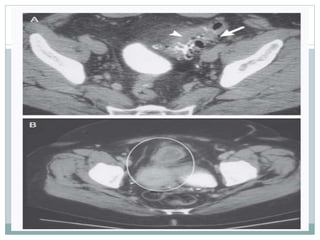

 La tomografía es recomendado en la examinación

inicial de imagen. Posee alta sensibilidad (93-97%) y

especificidad aproximadamente 99% para el

diagnostico; además permita determinar la extensión

del proceso.

 La presencia de divertículos, inflamación de grasa

pericolonica u otro tejidos, aumento del grosor de la

pared intestinal >4mm, o absceso peridiverticular es

fuertemente sugestivo de diverticulitis.

 TC también revela otros procesos inflamatorios por dolor

abdominal bajo, como apendicitis, absceso tubo ovárico o

enfermedad de crohn.

 Para pacientes con absceso peridiverticular de >4cm de

diámetro (Hinchey estadio 2) se puede indicar drenaje

percutáneo guiado. Este procedimiento elimina o reduce

la zona del absceso, con disminución del dolor, resolución

de la leucocitosis usualmente en varios días.